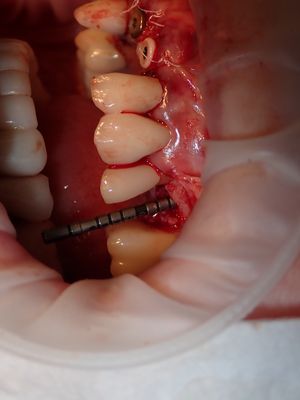

NSankhyan - immediate 13, impls 1121 and 25 with grafting

13 exo, loss of labial plate, implant placed buccal region grafted with sticky bone and collagen membrane soaked in prf fluid. 11/21 limited Labial-palatal width of bone, ridge split to 5mm, osteotomies prepared to about 2mm, remainder with densah drills, implants placed with ample bone, buccal grafted with same sticky bone. densah drills used for apical portion of 25 implant, soft bone, implant placed